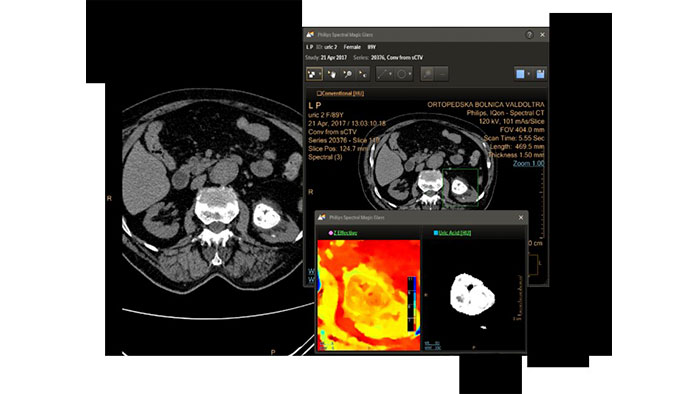

IQon Spectral CT Functionality

Provides the ability to run cardiac segmentation on different energy levels, compare vessel curves with various spectral data types, and enhance the visual assessment of coronary vessel patency.

Review spectral data in a range of not spectral-enhanced CT applications

Allows retrospective use of spectral data that was saved in a series of spectral base images (SBI). The fast launch of LMG allows review and identification of the most relevant results to be launched into the application for further analysis.

IQon Spectral CT is the only scanner to offer CT Spectral Light Magic Glass and CT Spectral Magic Glass on PACS, helping radiologists review and analyze multiple layers of spectral data at once, including on their PACS.